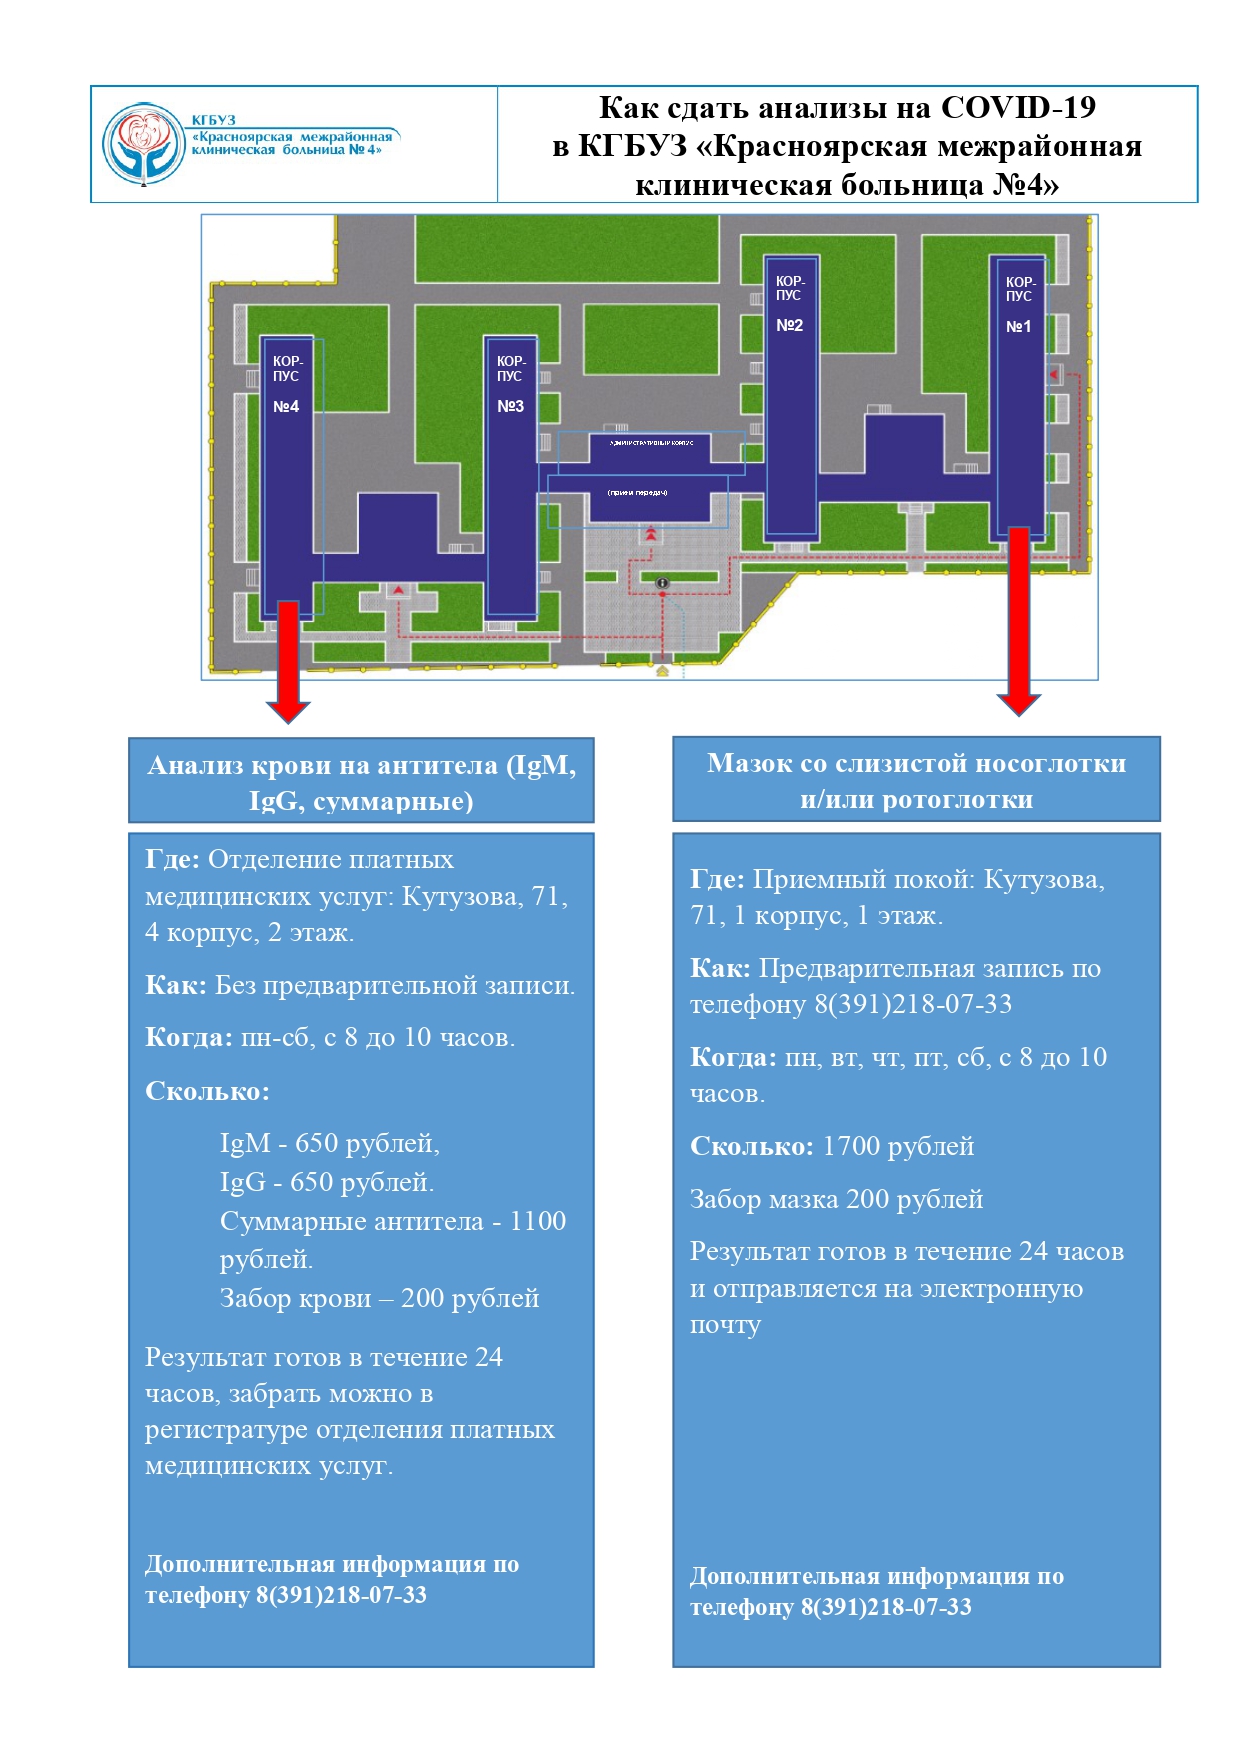

Как сдать анализ крови в КГБУЗ "КМКБ №4"?

Подробнее...

Горожане смогут сдать мазок на коронавирус в больнице на Кутузова

Подробнее...